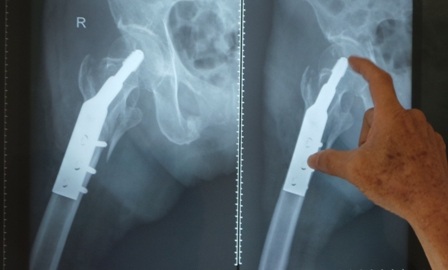

Qua chẩn đoán hình ảnh, bác sĩ phát hiện liên mấu chuyển cổ xương đùi phải của bệnh nhân gãy thành 4 mảnh lớn và nhiều mảnh nhỏ. Ngoài chấn thương trên, cụ bà còn bị suy thận mạn giai đoạn cuối, đái tháo đường, tăng huyết áp, bệnh tim thiếu máu cục bộ. Trước tình trạng cơ địa suy kiệt của người bệnh, ban đầu bác sĩ dự tính sẽ điều trị bảo tồn. Tuy nhiên, đây chỉ là phương án tạm thời nếu không được can thiệp triệt để, cụ bà sẽ phải nằm một chỗ chấp nhận cái chết đến từ từ vì nhiễm trùng, suy hô hấp.

Dưới sự hỗ trợ của màn hình tăng sáng (C-ARM) ê kíp phẫu thuật đã mở vết mổ 4cm, thực hiện thành công thủ thuật kết hợp xương nẹp vít cho người bệnh. 2 tuần sau khi được can thiệp, hiện bệnh nhân đã ngồi dậy được, sức khỏe đang bình phục tốt.